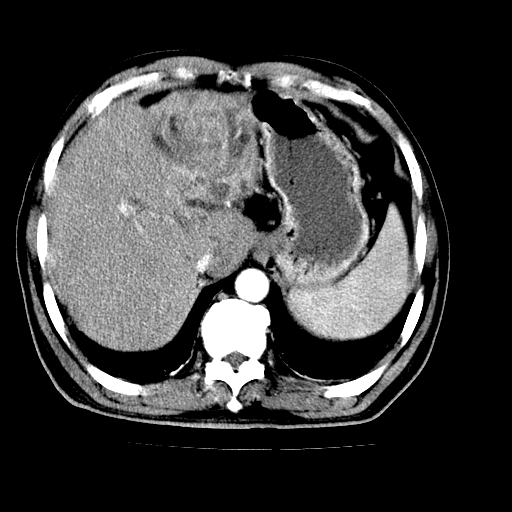

男,66岁,上腹部不适、黄染一周。彩超示:肝左叶占位,肝内胆管扩张,胆总管扩张,胆总管占位?

肝左叶不规则软组织肿块影,边缘不规整邻近肝实质受累分界不清;肝内胆管(左叶)明显扩张成“软藤状”,诊断:肝左叶胆管细胞癌。

肝左叶占位性病变,并胆管扩张,符合胆管细胞癌ct表现,门脉左支受累,左肾囊肿。窗宽太窄了,其他的看不清

左叶胆管细胞癌累及胆总管,门脉左支受侵,慢性胆囊炎胆结石,左肾小囊肿

肝左叶不规则软组织肿块影,边缘不规整邻近肝实质受累分界不清;肝内胆管(左叶)明显扩张成“软藤状”,诊断:肝左叶胆管细胞癌。胆囊钙乳症。

胆囊缩小,其内胆汁浓缩,也提示梗阻部位应该位于胆囊管起始部以上或是胆囊管受累及,支持肝外胆管癌。